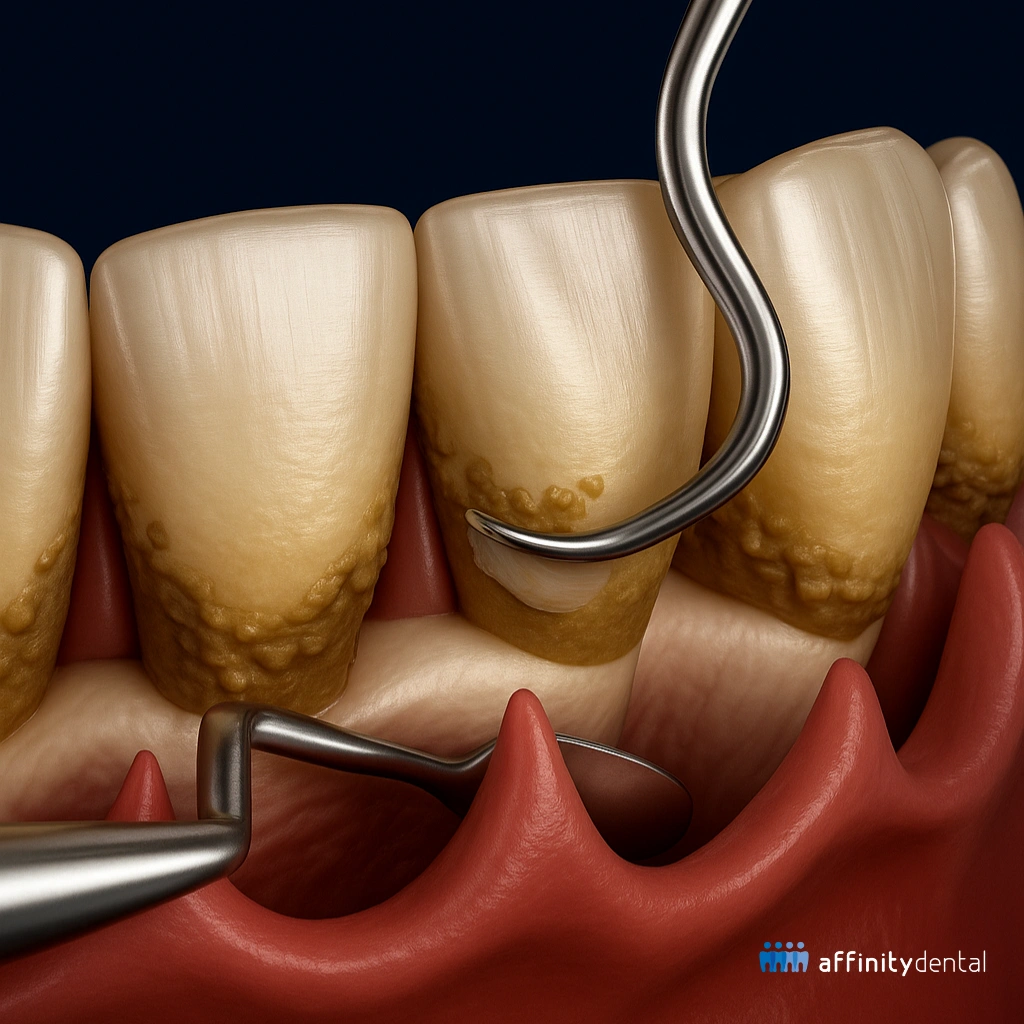

Scaling and Root Planing (SRP) is a non-surgical deep cleaning procedure used to treat gum disease, especially in its early to moderate stages. It involves cleaning below the gumline to remove plaque, tartar (calculus), and harmful bacteria that contribute to inflammation, infection, and gum recession.

• Root planing smooths out the root surfaces of the teeth to help gums reattach and heal, while also making it harder for bacteria to stick again in the future.

Using manual instruments or ultrasonic scalers, your dentist will carefully remove plaque, tartar, and bacteria from below the gumline and around the tooth roots.

The root surfaces are then smoothed to help the gums heal and reattach, and to discourage bacteria from returning.